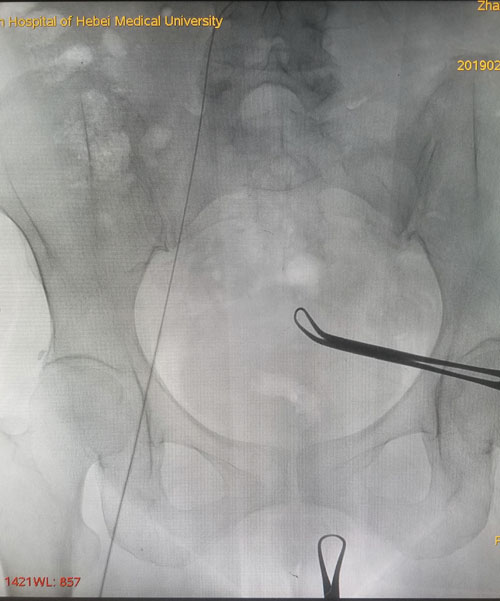

術(shù)中DSA評(píng)估導(dǎo)絲走形